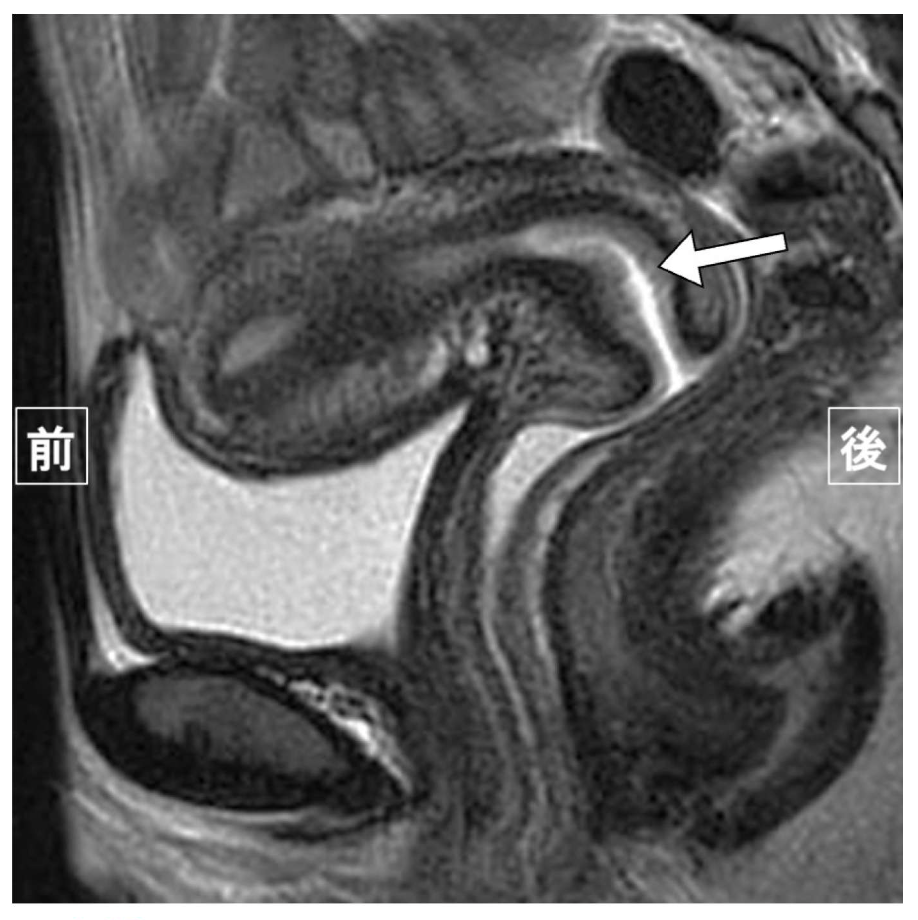

問題 33 子宮のT2強調矢状断像を示す。矢印が示す解剖構造はどれか。(不適切問題)

1. 子宮頸管

2. 頸部間質

3. 外層筋層

4. 子宮内膜

5. 頸管粘膜